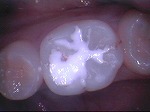

◆コンポジット充填

~修復前~

コンポジットレジン充填

~修復中~

~修復後~

~臼歯術前~

~臼歯術後~